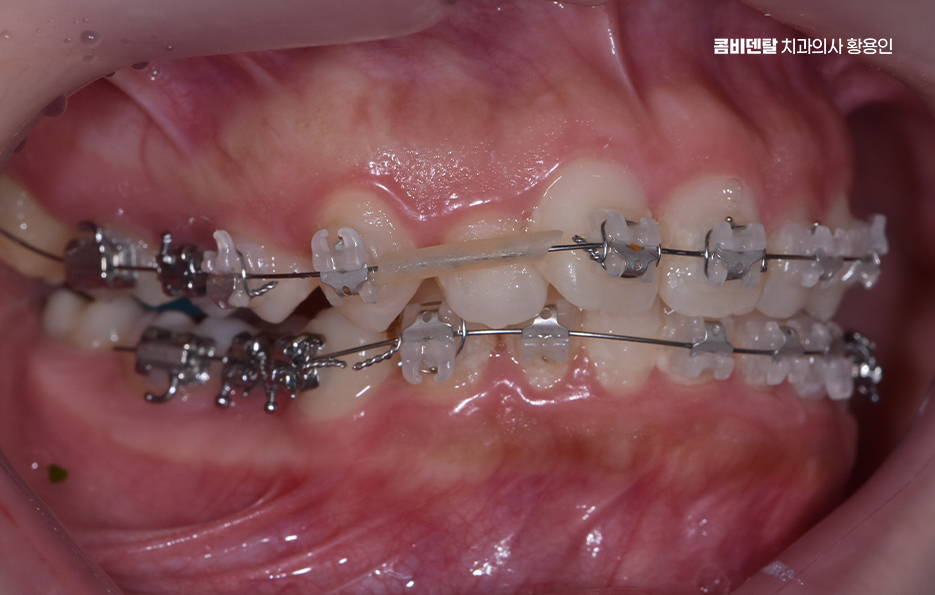

비발치 돌출입 교정에서 주로 사용되는 방법 중 하나는 악궁 확장으로 치아가 나 있는 폭을 넓혀서 공간을 확보한 뒤, 치아를 재배열하는 방식인데 이 방법은 공간을 만들어 발치 없이 교정을 진행할 수 있다는 장점이 있지만, 무리한 확장은 잇몸이나 치아 뿌리에 부담을 줄 수 있기 때문에 한계 범위 안에서만 적용되고 있어요

또 다른 비발치 방법은 어금니를 뒤쪽으로 이동시키는 방식으로 어금니를 뒤로 보내서 앞니가 들어갈 공간을 만드는 개념이며 치간 삭제 라는 방법도 있는데 치아 사이의 공간을 미세하게 조절하여 치아의 건강은 해치지 않으면서 치아의 이동 공간을 확보하는 방식이라 할 수 있었어요

하지만 비발치 돌출입 교정에는 분명한 한계점도 있는데 우선 돌출입이 심한 경우에는 돌출 개선 효과의 한계로 발치 교정에 비해 치아를 뒤로 이동시킬 수 있는 양이 제한적이기 때문에, 돌출이 심한 경우에는 기대했던 만큼의 변화가 나타나지 않을 수 있어요.